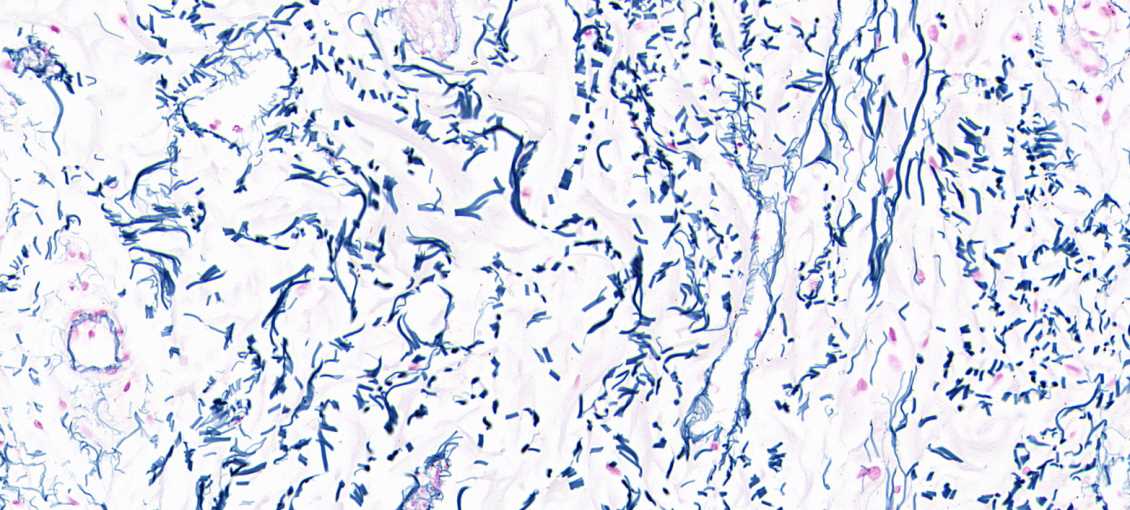

皮肤组织常见染色

特殊染色:甲苯胺蓝、天狼猩红、weigeirt、维多利亚蓝、MASSON等染色